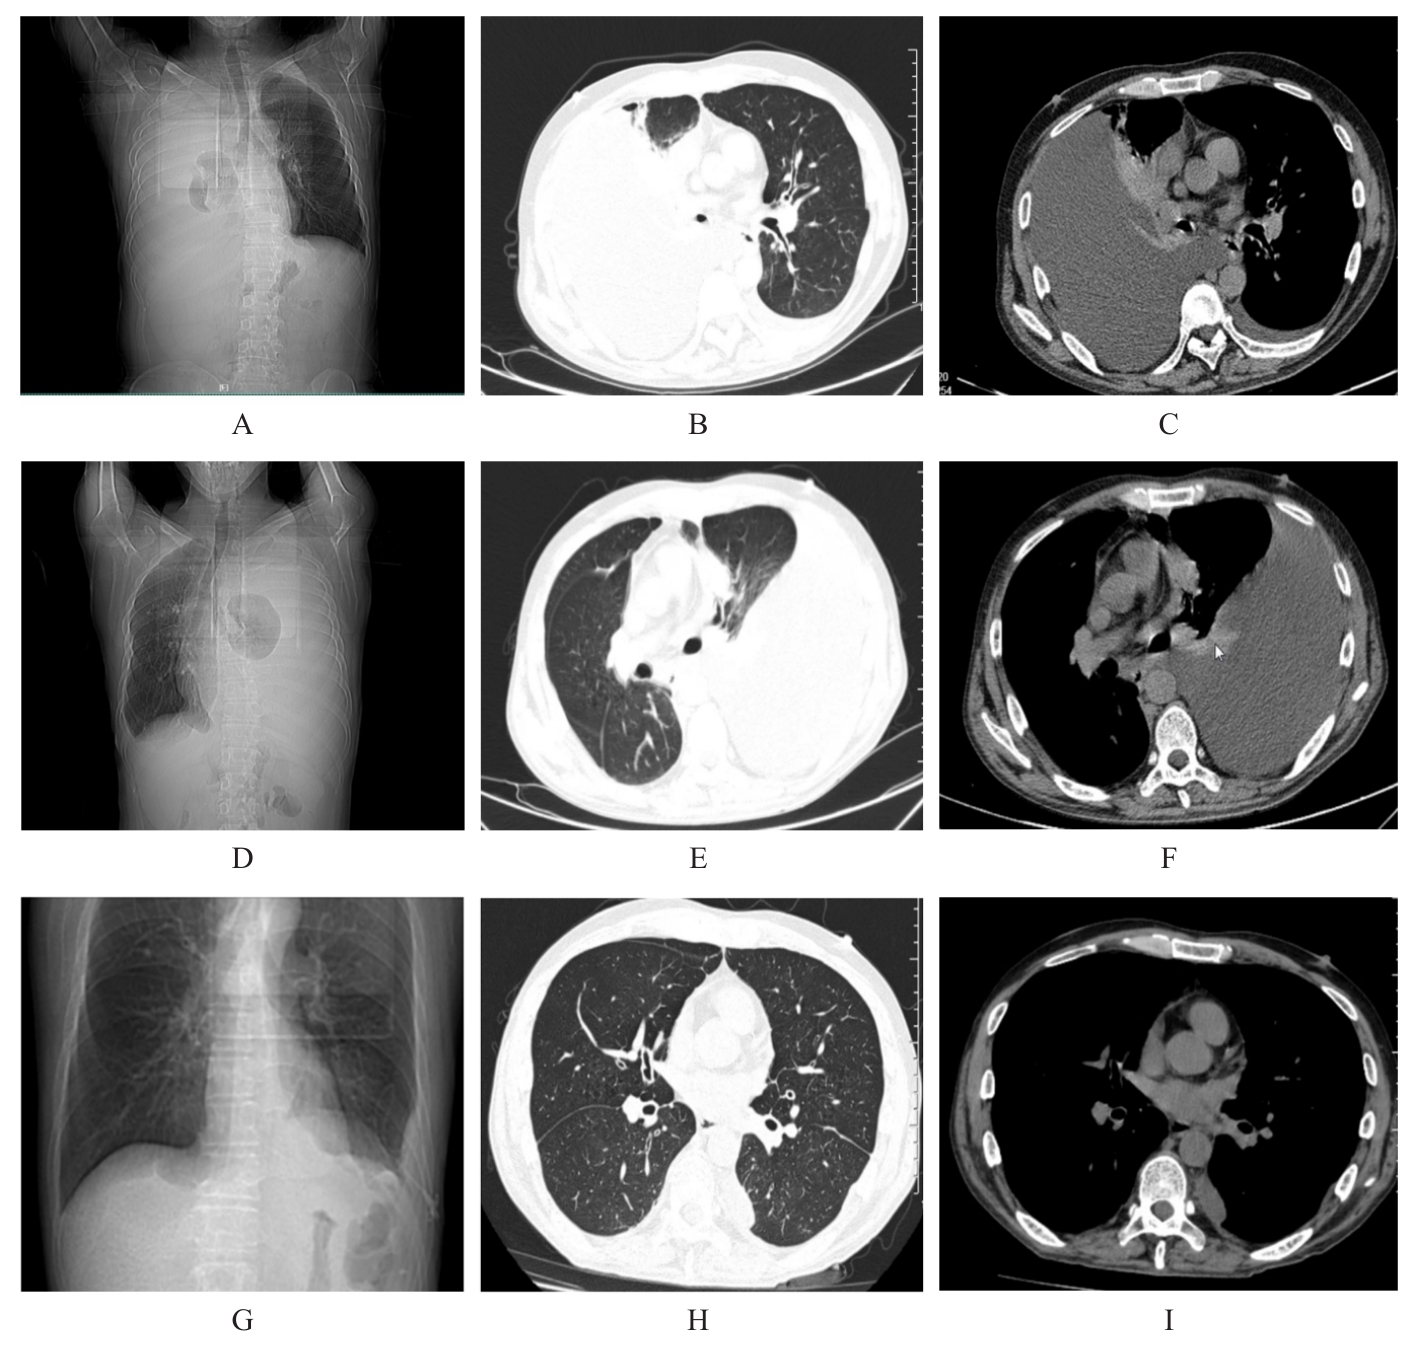

Luyao WANG,Chenxi ZHAO,Wanze ZHANG,Linlin LIU.

Second primary tracheal adenoid cystic carcinoma:A case report and literature review

[J]. Journal of Jilin University(Medicine Edition), 2025, 51(1): 215-221.